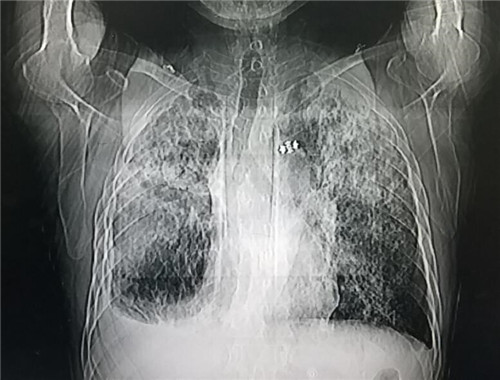

听取主治医生汇报过程中,李庆华主任单刀直入的指出患者肺部疑似尘肺,要求医生再次询问患者工作履历,综合患者煤矿、砖厂、化肥厂工作经历以及相关指标,李庆华主任考虑是尘肺导致双肺纤维化合并重症肺炎,对现有抗生素使用方案给予指导后,强调心衰注意事项,有的放矢的纠正血氧、预防肝肾衰竭。